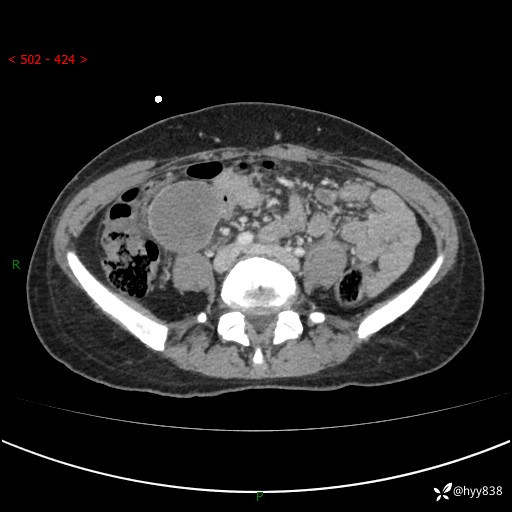

年轻女性,发现腹腔肿物1周。圆圆的肿物,诊断有难度---结果公布~

主诉:发现腹腔肿物1周

现病史:患者自诉于1周前无明显诱因出现剑突下间断性隐痛,尚可忍受,不向其它部位放射,无恶心呕吐、腹泻便秘等不适,于当地市第二人民医院就诊,行CT结果示:1.右中腹占位,间叶组织来源可能2.小肠梗阻3.盆腔积液4.腹腔积液5.副脾6.肝囊肿;于荆州二医行抗炎,抑酸,护胃,补液等对症支持治疗;患者病情好转,今为求进一步诊治,遂来我院门诊就诊,门诊以“腹腔肿瘤”收入院。 起病以来,患者精神、睡眠、饮食一般,大小便正常,近期体力体重无明显改变。

腹部CT增强(外院平扫)